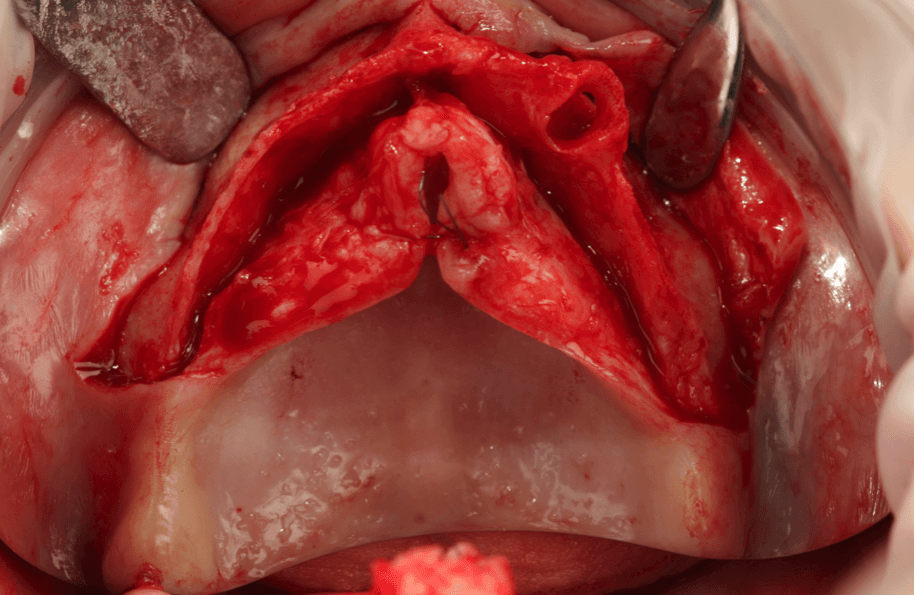

A true clinical residency where you plan, assist, and perform real full-arch surgeries under the guidance of Dr. Pedro Rodrigues and his team. Gain the confidence and skills to elevate your practice.

Exclusive 1-on-1 training where you perform 4 full-arch surgeries (2 as main surgeon and 2 as assistant) under Dr. Pedro Rodrigues’ direct supervision.

Gain hands-on experience performing full-arch surgeries under the direct supervision of Dr. Pedro Rodrigues.

Hands-on training: operate 4 full-arch surgeries (2 as main surgeon and 2 as assistant) with Dr. Pedro Rodrigues

Operate 4 full-arch surgeries (2 as main surgeon and 2 as assistant) under supervision

Advanced cases: from challenging to extreme